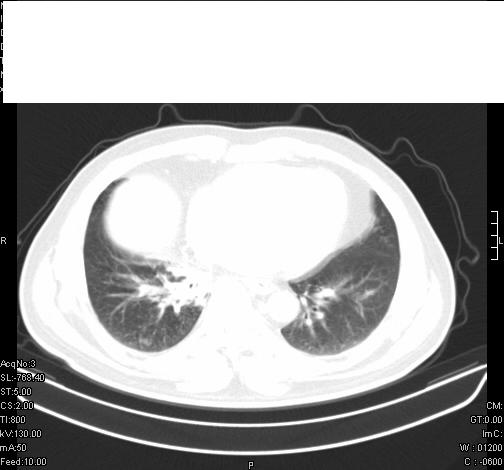

前几天,发了患者的平扫片,患者抗炎一周后增强扫描。右中叶病灶吸收明显,但下叶病灶未见明显吸收。右肺门可见结节影,看来凶多吉少

右肺下叶支气管管腔狭窄,管壁增厚,右下肺见斑片状高密度影,考虑右侧肺门中心肺癌伴阻塞性肺炎

右肺下叶散在的斑片状致密影,下叶支气管变窄。考虑:右肺慢性炎症。

还是考虑右肺中央型肺癌可能性大

考虑右肺中央型肺癌可能性大

既然抗炎治疗有效,可继续治疗;右肺下叶支气管管腔狭窄,管壁增厚,右下肺见斑片状高密度影,右侧主支气管后见结节影(淋巴结?),肺癌不能排出。